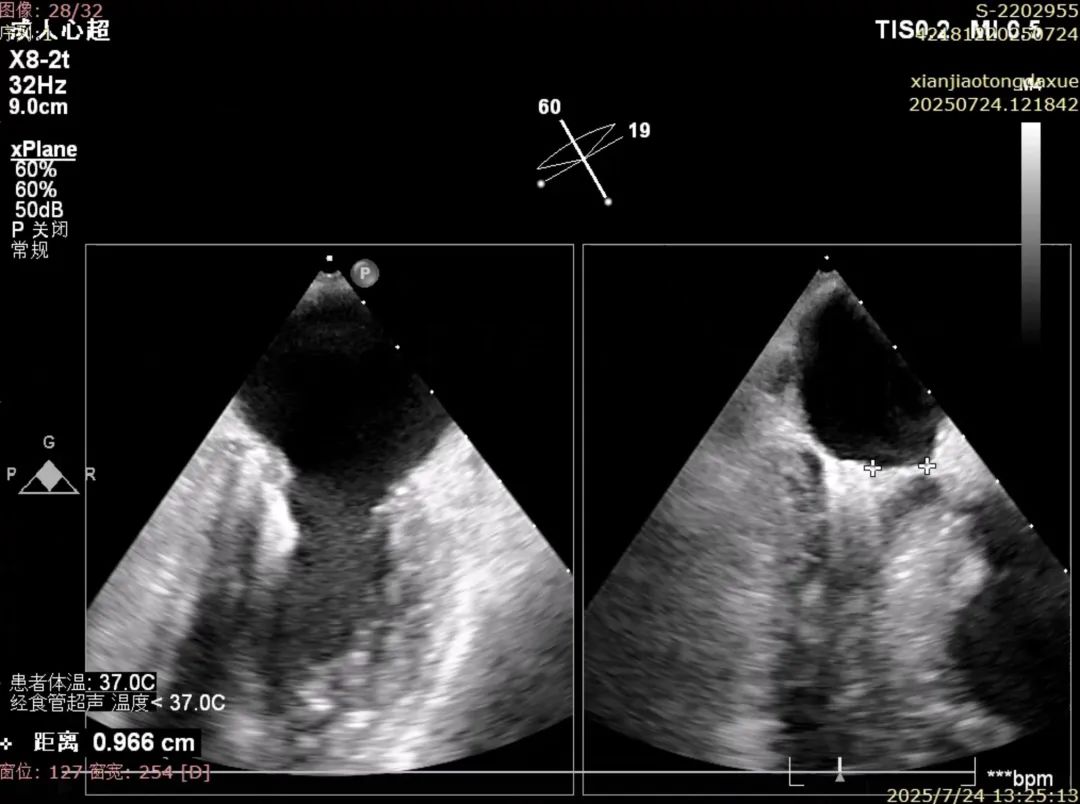

确认夹合位置及效果

术后夹合数据确认,达到预期效果